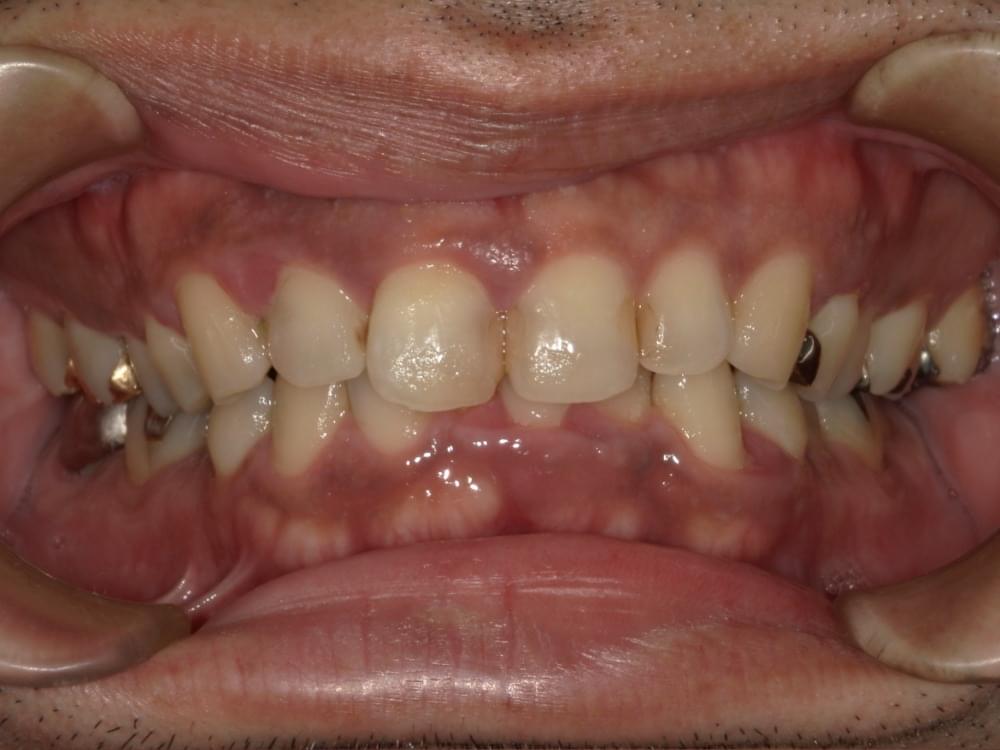

歯周病治療プログラムの治療例3

レーザーとCTといった他院にはない設備があるから他の医院ではやってくれない所をやってくれそうと来院。他院では丁寧にやってくれなかった。

けれどこちらではすごく丁寧にやってくれているとHPを見て分かった

治療の概要

治療内容

行動科学に基づき、「自分の歯は自分で守る」という意識改革や行動変容を促しながら、スケーリングや歯ブラシ・フロス指導を行いました。

治療期間・回数・時間

1.5ヶ月・5回・計5時間

費用

29,500円+税

リスク・副作用

歯肉の痛み・出血